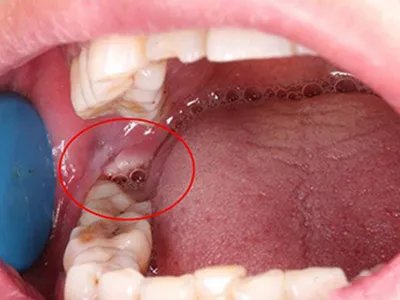

智齿冠周炎表现为冠周软组织及牙龈出现红肿,磨牙后区有一隆起的肿块,顶端发白,周边发红,口腔检查时发现一萌出方向异常的智齿,自觉局部触痛明显。智齿冠周炎牙龈糜烂图

智齿冠周炎患者磨牙后区萌出第三个磨牙周围牙龈组织肿痛甚至溃烂发白,多是由于阻生等原因导致其萌出不全,形成牙周袋,牙周袋内容易积存食物及细菌导致。智齿冠周炎牙龈化脓图

智齿冠周炎患者可出现磨牙后区疼痛,检查可见智齿萌出不全,周围牙龈肿胀,部分患者可有脓肿形成,白色的脓液可从牙周袋内溢出。智齿冠周炎相关知识症状智齿冠周炎具有磨牙后区肿痛、吞咽、进食时加重、不同程度的张口受限等症状。口腔检查时可见有萌出位置及方向异常的智齿,冠周软组织红肿甚至溃烂,有时可见齿痕或者脓肿,局部触痛明显。病因智齿冠周炎主要与口腔卫生差等因素有关。临床上智齿在萌出过程中形成与口腔相通的盲袋,盲袋内易存储食物残渣、唾液、细菌,在适宜的口腔温度和湿度环境中很容易滋生细菌,容易引发冠周智齿炎。治疗智齿冠周炎可遵医嘱进行冲洗,如双氧水或温热生理盐水,冲洗后可用碘甘油、三氯醋酸等药物涂抹。日常可使用温热水含漱,改善局部血循环,缓解肌内疫挛,促使炎症消散。症状严重时可遵医嘱使用抗生素,如头孢克洛颗粒、阿莫西林胶囊等。